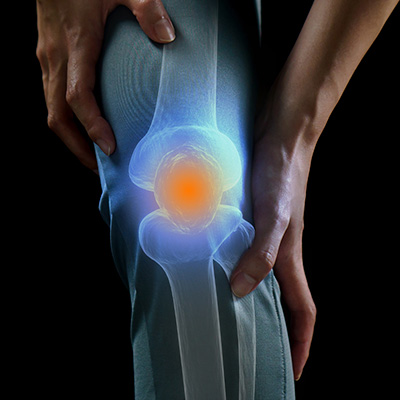

반월상연골손상이란?

무릎관절은 대표적인 체중 지탱 관절로

무릎 사이에서 충격 흡수 기능을 하는 구조물을

반달 모양을 닮았다고 해서 반월상연골이라고 합니다.

무릎에 심한 외상을 겪거나 장기간 무릎에 충격이

누적되면 이 연골이 손상을 받습니다.

경사로나 계단을 내려갈 때 무릎 깊숙한 곳에서 발생하는

통증이 주로 반월상 연골로 인한 통증입니다.

심한 경우 손상된 연골 구조물이 자극이 많이 되면

무릎에 물이 차기도 합니다.